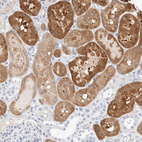

Immunohistochemistry analysis in human cerebral cortex and skeletal muscle tissues using HPA024099 antibody. Corresponding GDA RNA-seq data are presented for the same tissues.